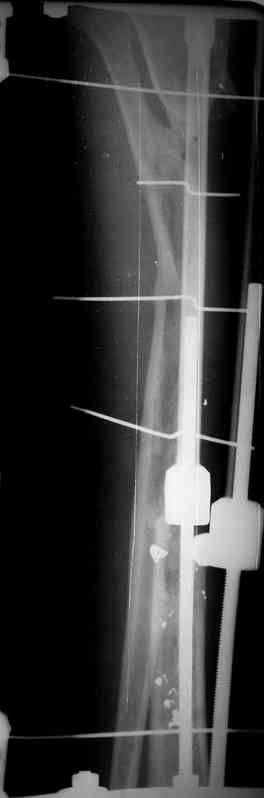

5. Ну и чтобы не быть голословным. Молодой человек подорвался на фугасе (Чечня, 2005 год). Свежие рентгенограммы:

Соответственно ожоги и дефект мягких тканей, переломы костей стопы и пр. Наложили аппарат

Илизарова (как придется), хирургически обработали и героически заживляли мягкие ткани с многочисленными кожными пластиками. В итоге через полгода я принял его вот таким:

Реализовал описанную выше методику, и в итоге вот что получилось. Высылаю лишь прямые проекции,

Очень пригодились карбоновые кольца (Джолдас -огромное спасибо, я твой должник!!!), поскольку остеопороз дистального отломка был просто невероятный. На цифровом рентгене с трудом угадывались контуры.

Рентген в процессе перемещения - внизу карбоновые кольца, тракция фрагмента спицами с упором.

внешний вид в аппарате - не завершающем этапе, сначала стопа тоже была фиксирована в аппарате.

Сейчас аппарат сняли, но случай ещё не завершенный.

Признаюсь честно, не совсем уверен в прочности консолидации на стыке косточек. Кроме того, укорочение в районе 6 см. Сейчас реабилитация - ходит опираясь на ногу с одним костылем.

Продолжение, видимо, будет... Возможно, будем удлинять.